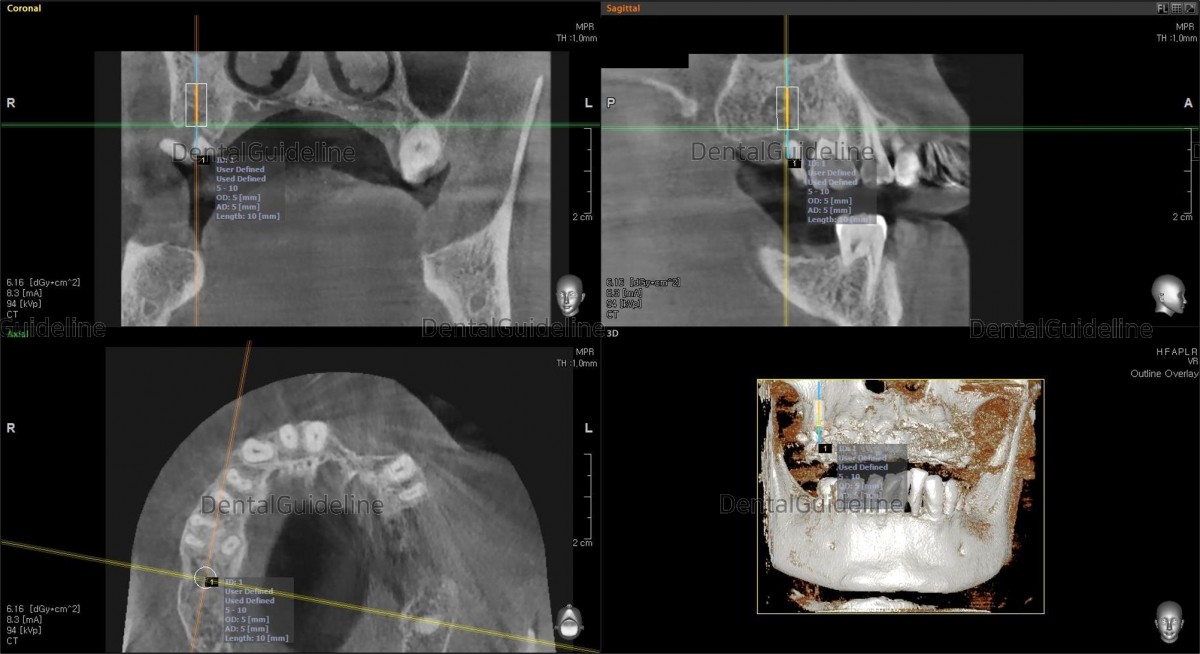

- Simple simulation on the CBCT image.